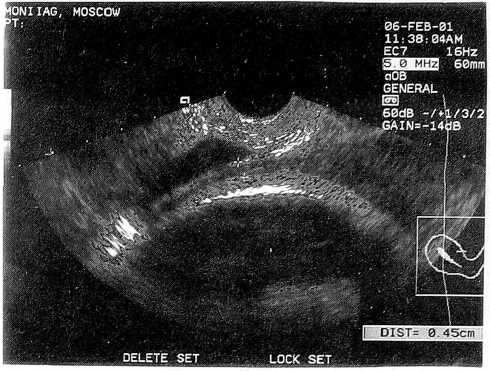

Как показали наши исследования, несостоятельными являются и так называемые «толстые» рубцы. При анатомической полноценности (толщина их была не менее 5—7 мм) в них преобладали элементы соединительной ткани (морфологическая неполноценность), и роды у этих женщин в связи с функциональной неполноценностью рубца чаще всего заканчивались повторной операцией (рис. 4).

Рис. 4. Морфологически неполноценный (соединительнотканный) рубец на матке